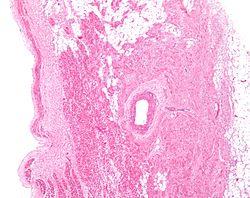

Low magnification micrograph of a sinoatrial node (central on image), surrounding the sinuatrial nodal artery (on lumen in the image). H&E stain.

The sinoatrial node surrounds the sinoatrial artery, which can run centrally (in 70% of individuals) or off-center within the node.[3]